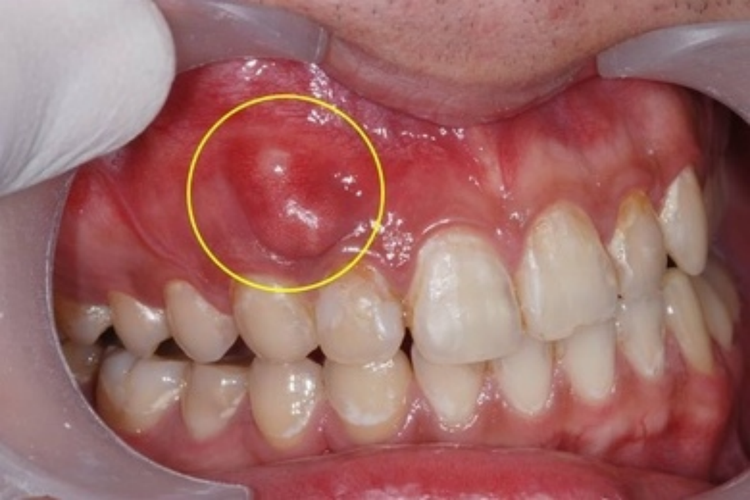

根尖周囊肿:囊肿大小不等,由豌豆大至鸡蛋大。小囊肿不易被发现。囊肿发展较大时,根尖部牙龈呈半球形隆起,形状不规则,扪诊时有乒乓球感。